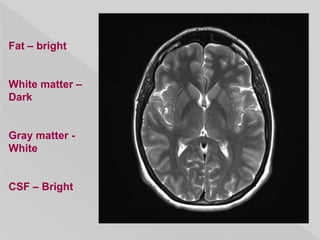

 repetition time (TR): long

 echo time (TE): long

 flip angle: less important than with T1

weighting

 Fat: intermediate-bright

 Fluid: bright

Fat – bright

White matter –

Dark

Gray matter -

White

CSF – Bright